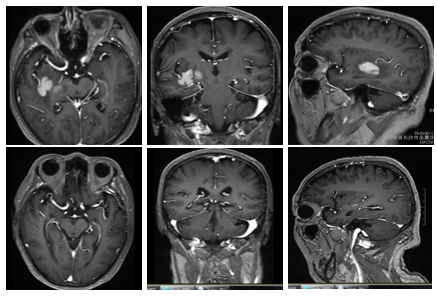

治疗约60天后,MRI对比图如下所示:

上. 三线治疗后,疾病进展后的MRI图

下. 四线治疗后,达到CR的MRI图